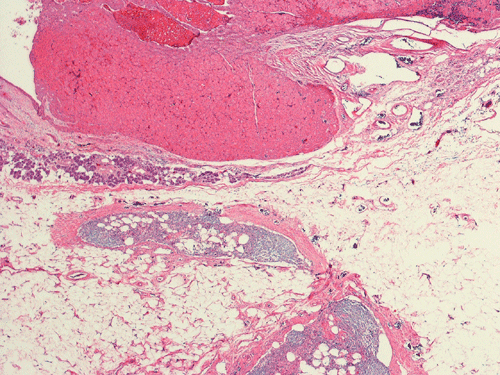

Pathology of the Case: Grossly, the tumor was a small 1 x 2 cm well demarcated nodule embedded within the mid portion of the salivary gland. There is no true capsule (Panel A). The tumor cells arrange in solid sheets and without specific pattern formation (Panel B and C). There is no collagenous tissue within the tumor. The tumor cells are polygonal and rather homogeneous in size. They have low-grade, centrally located nuclei (Panel D), finely granular and distinctly eosinophilic cytoplasm. The granular feature is best appreciated in the cytoplasmic preparation that is prepared while the tumor is being examined before fixation (Panel E).  There is no necrosis or mitotic figures.

Grossly, oncocytomas are well-circumscribed, well-demarcated, round to lobulated nodules, averaging 3-4 cm in size. Oncocytomas arising from major salivary glands are usually encapsulated and those arising from minor salivary glands have less well defined borders and are usually not encapsulated. The cut surface has a typical tan-brown color. Benign oncocytomas frequently have with a central star-like scar.

Microscopically, oncocytes have a very characteristic appearance with granular eosinophilic cytoplasm due to marked increase in the number of mitochondria mitochondria, pleomorphism of mitochondria, and a paucity of other organelles. The tumor cells have little variation among different tumors or different part of the same tumor. Characteristically, the tumor cells are rather uniform and polygonal in shape. The cytoplasmic membrane can be readily recognized. The nuclei are usually round, centrally located, and nucleoli are present. The cells are arranged in uniform solid sheets without a specific pattern  or they may aggregate into clusters, and sometimes they form duct-like structures. Thin fibrovascular septa are present. Oncocytomas may have a clear cell component secondary to accumulation of cytoplasmic glycogen 6. A PAS stain with and without diastase digestion will be very helpful in recognizing the glycogen. High grade nuclear atypia is only seen exceptionally. Phosphotungstic acid hematoxylin (PTAH) is a good stain that would stain the mitochondria dark. However, the stain is rarely called to service for this purpose as the cytoplasm is typically characteristic enough for recognition without special stain. In clear cell variants, however, PTAH may help. Mitotic figures are not readily seen. In most situations, the diagnosis of oncocytoma is not a particularly challenging one.